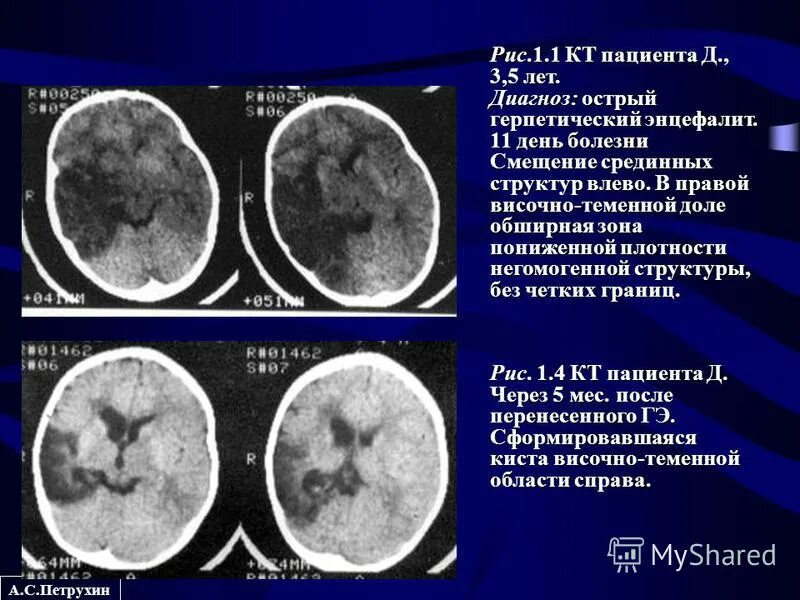

Очаг ограничения диффузии